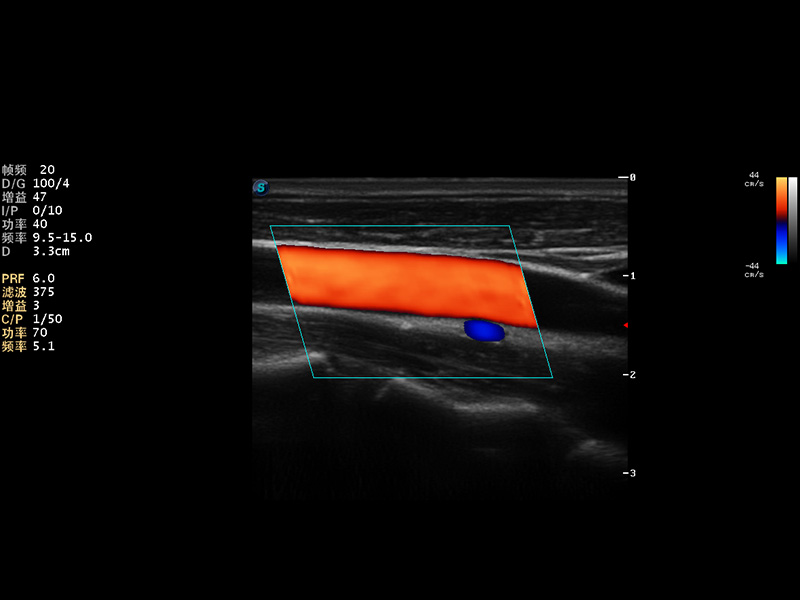

S9便携式彩色多普勒超声诊断仪是公海贵宾会员检测中心医疗研发的高端便携彩超设备,外观设计新颖、产品性能卓越。S9在便携超声领域采用了突破传统的触摸屏交互设计,并以先进的软件硬件技术和设计理念,为您带来清晰的图像质量、稳定的工作性能和便捷的操作体验。

AutoC智能血流追踪